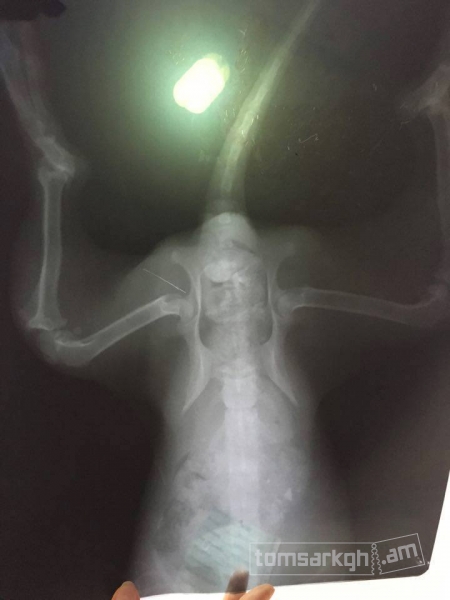

Արևիկին Դինգո կամավորները վերցրին իրենց խնամքի տակ և փորձեցին բուժել, սակայն ապարդյուն։ Մի քանի կիլոգրամ կշռող այս հրաշքն ունի մի շարք խնդիրներ, որոնք ցավոք հայաստանյան պայմաններում բուժել հնարավոր չէ։ Վնասված է Արևիկի ողնաշարը։ Դինգո թիմը չցանկացավ հանձնվել, ուստի որոշում կայացվեց Արևիկին ուղարկել Միացյալ նահանգներ բուժման նպատակով։ Ակնհայտ է, որ մեզ հարկավոր է դրամական օգնություն, ուստի մեր պայքարին միացան նաև մի շարք հայտնի մարդիկ, ովքեր սիրով համաձայնեցին մասնակցել մեր կազմակերպած միջոցառմանը, որի ողջ հասույթը կփոխանցվի մեր շնիկի փրկության գործին։